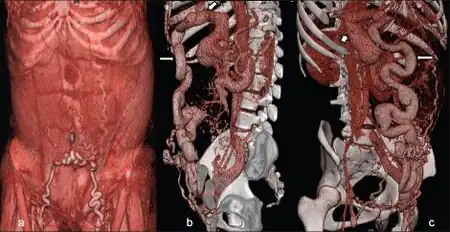

| a) Caput medusae b,c) paraumbilical vein being fed by left branch of portal vein | |